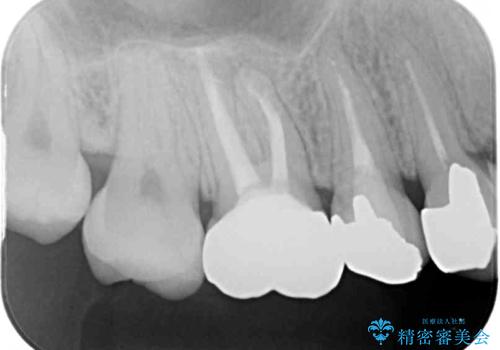

- 笑ったときに見てしまう上顎奥歯の銀歯を気にして来院された患者様です。

折角セラミッククラウンを装着するので、根管治療を行った後に補綴治療を行うこととしました。

他にも目立つ銀歯がありましたが、最も気にしている2本を優先して行うこととしました。